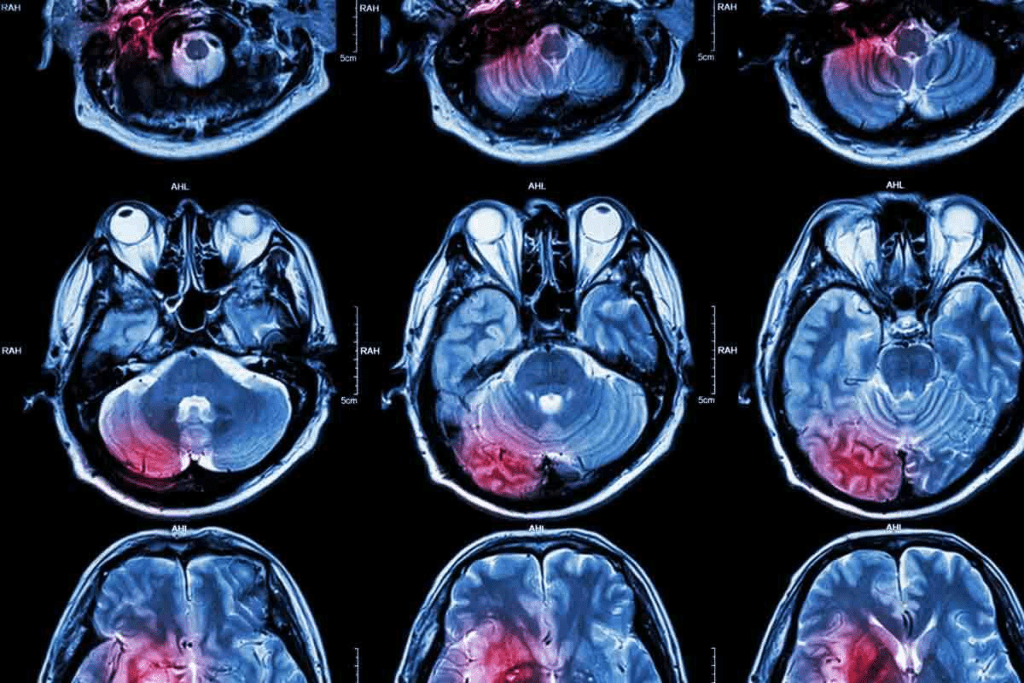

Interpreting a Mass on Brain MRI: What It Means

When a mass shows up on a brain MRI, it’s important to know what it means. It could be a sign of different things, like tumors. Where and how the mass looks is key to figuring out what it is.

Common MRI Findings: Shadows, Knots, and Lumps

Brain MRI scans can spot many kinds of problems, like shadows, knots, or lumps. These can mean anything from harmless cysts to serious tumors. For example, a knot in the brain might be a tumor or another kind of growth.

Not every shadow or lump is cancer. But, any unusual finding needs to be checked out to find out why it’s there.

When to Be Concerned About MRI Results

Seeing a mass on an MRI can worry people. How worried you should be depends on the mass’s size, where it is, and what it looks like. For instance, a tumor on top of the brain or a lump on the forehead might mean different things, depending on if it’s bad or not.

The Diagnostic Process After Finding a Mass

When a mass is found on a brain MRI, doctors start a detailed check-up. They might use more tests, like PET scans or special MRI scans, to learn more. Sometimes, they need to take a sample of the mass to see if it’s cancer.